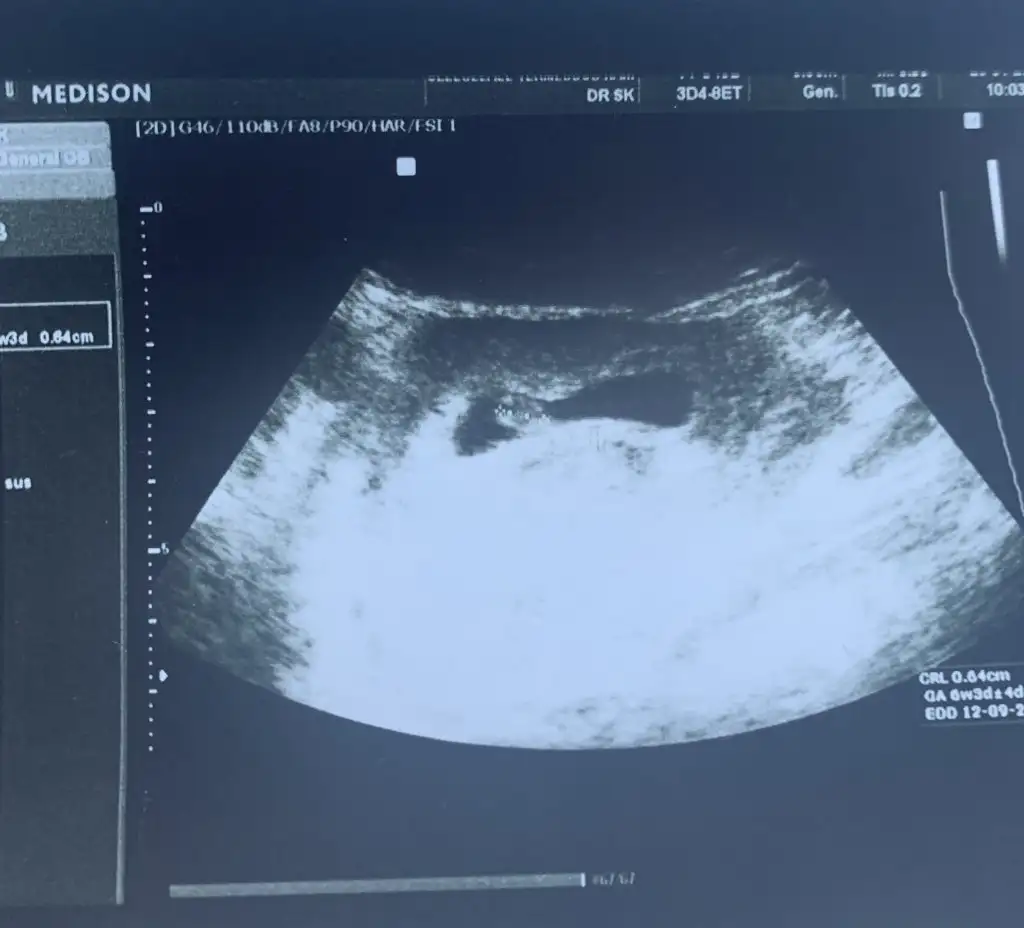

Benim sadece kese var şu an canım..kalp atışlarını daha duymadık erken gitmiştim, vajinadan bakıldı..